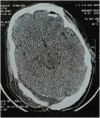

Supratentorial-infratentorial epidural hematomas (SIEH) are a rare occurrence following traumatic head injuries, representing only 2% of traumatic epidural hematomas. Given the unique anatomical characteristics of the infratentorial region, mainly its small size, surgical intervention is commonly undertaken to alleviate the pressure on the posterior fossa components. Consequently, there is ongoing debate surrounding the optimal surgical approaches.In this report, we present four cases of SIEH that were treated surgically. Furthermore, we conduct a comprehensive review of existing literature, encompassing clinical, radiological, and therapeutic aspects associated with this condition.SIEH are uncommon post-traumatic lesions that require urgent and individualized management on a case-by-case basis, as guided by multiplanar cerebral computed tomography scan findings. Preoperative planning is essential; however, intraoperative exploration and identification of transverse sinus and torcula lesions are crucial for optimal patient care. The surgical approach may be modified intraoperatively based on the nature and extent of these lesions. In all cases, prompt hematoma evacuation and meticulous hemostasis are the two primary objectives of this surgery.